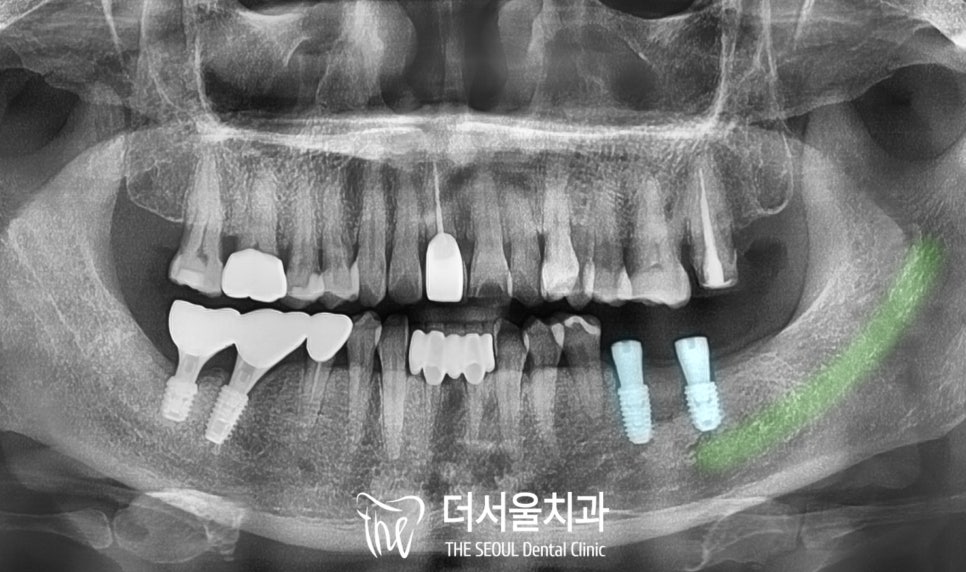

4. 픽스처 식립

태평역치과 에서

디지털 임플란트를 계획한 대로

식립을 마친 모습을 보겠습니다.

보이는 것처럼

하치조 신경과 거리를 유지하며

예측했던 곳으로

두 개의 픽스처를 심었습니다.

또한 부족한 곳은 일부

추가 골이식을 통해 보강해 드렸습니다.